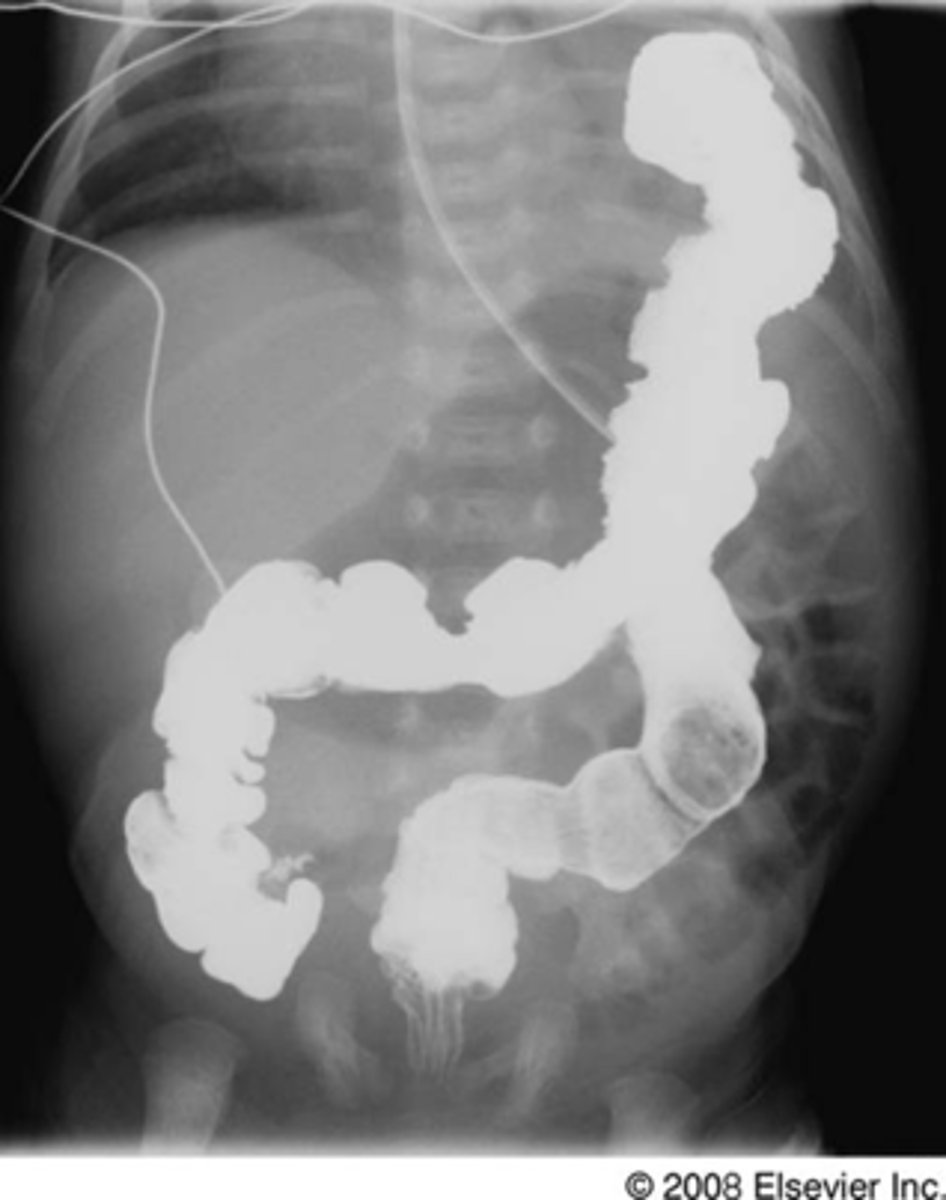

Diaphragmatic rupture

knowt flashcard image